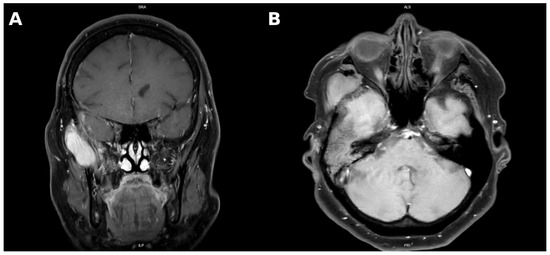

Extracranial Extension of a Convexity Meningioma into the Temporal Fossa: A Rare Case Report and Literature Review

Background and Clinical Significance: Meningiomas are among the most common primary intracranial tumors, usually benign and slow-growing. Extracranial extension is exceptionally rare, particularly when arising from convexity meningiomas extending into the temporal fossa. Such cases pose unique diagnostic and therapeutic challenges due [...] Read more.

Background and Clinical Significance: Meningiomas are among the most common primary intracranial tumors, usually benign and slow-growing. Extracranial extension is exceptionally rare, particularly when arising from convexity meningiomas extending into the temporal fossa. Such cases pose unique diagnostic and therapeutic challenges due to their atypical growth patterns and anatomical complexity. Case Presentation: A 63-year-old woman previously treated for a right temporal convexity meningioma with subtotal resection and Gamma Knife radiosurgery demonstrated progressive extracranial tumor growth over five years, while the intracranial component remained stable. MRI revealed infiltration of the temporalis and lateral pterygoid muscles and erosion of the temporal bone. Due to extensive extracranial involvement and limited neurosurgical accessibility, resection was performed by a maxillofacial surgical team through a preauricular approach. Intraoperatively, the tumor was encapsulated but adherent to the deep temporal fascia and zygomatic arch. The temporal branch of the facial nerve was identified and preserved. Histopathology confirmed a meningothelial meningioma, WHO Grade I, with low proliferative activity (Ki-67 < 1%). Postoperative recovery was uneventful, with transient facial nerve weakness that resolved within weeks. Conclusions: This report adds to the limited literature describing temporal fossa involvement by convexity meningiomas and illustrates the value of collaboration between neurosurgical and maxillofacial teams. Regular MRI surveillance every 6–12 months is advised for early detection of recurrence. Full article